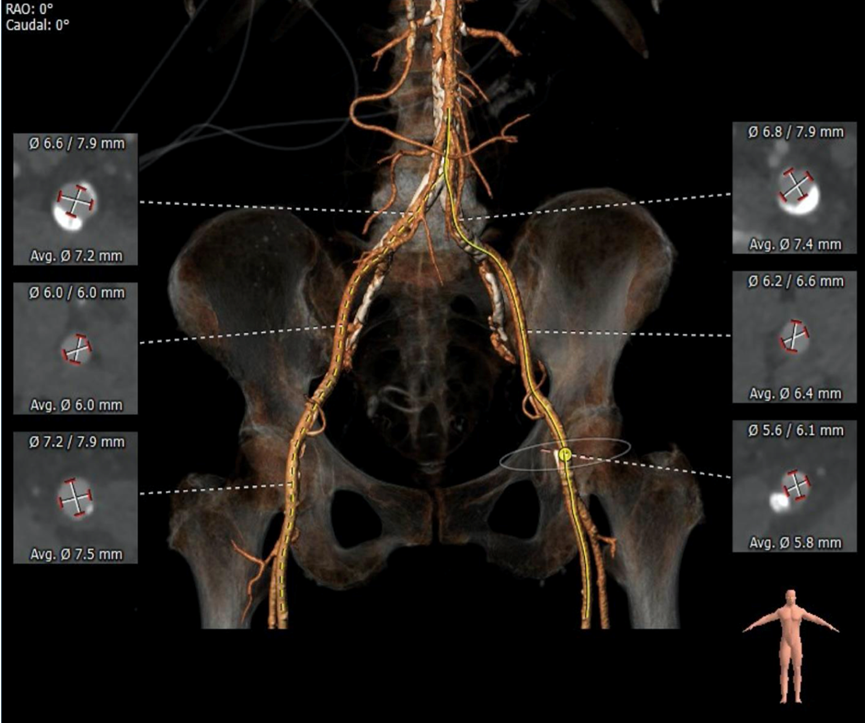

双侧髂总动脉可见近环形钙化,左侧股动脉穿刺区域可见孤立性较大钙化斑块,右侧散在钙化, 双侧入路血管管径尚可 ,符合血管入路条件。

3.外周入路钙化较为严重,双侧髂总动脉可见近环形钙化,左侧股动脉穿刺区域可见孤立性较大钙化斑块,右侧散在钙化;升主动脉、主动脉弓、胸腹主动脉管壁钙化严重。

外周血管及主动脉弓解剖: